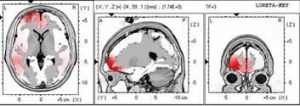

مثال اول : تصویر بالا مربوط به  اسکن خانم34 ساله ای  است که از 15 سالگی در هر سیکل ماهانه ، 5 روز از سردرد میگرنی رنج می برد.همین خانم بعد از درمان کامل چه در دوران پریودی و چه در بین سیکل های ماهانه اش حتی یک مرتبه هم از میگرن رنج نبرد.

مثال دوم : اسکن مغز بیمار 30 ساله  مبتلا به میگرن

قبل از درمان

بعداز درمان با rTMS